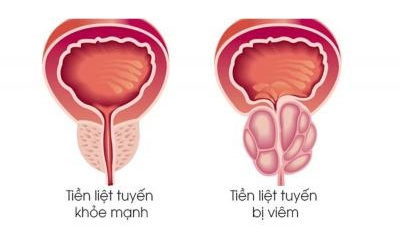

3. Tăng Cường Sinh Lý Và Sức Khỏe Sinh Sản

Một trong những lợi ích của Cordyceps Sinensis với sinh lý là khả năng tăng cường sinh lực và hỗ trợ sức khỏe sinh sản. Đối với nam giới, Cordyceps Sinensis giúp cải thiện chức năng thận, tăng cường sức mạnh và khả năng tình dục tự nhiên. Điều này là nhờ vào tác dụng kích thích tuần hoàn máu và sản xuất hormone sinh dục.

- Cordyceps Sinensis tăng cường sinh lý: Cordyceps Sinensis giúp nam giới cải thiện sinh lực, giảm thiểu tình trạng mệt mỏi và tăng cường năng lượng.

- Hỗ trợ sinh sản: Loại thảo dược này còn có thể cải thiện chất lượng tinh trùng, giúp nâng cao khả năng sinh sản.